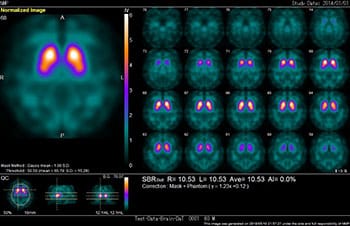

当院では、Cannon社製SymbiaE装置2台が稼働しています。主に骨シンチや負荷心筋シンチの検査ですが、他にもさまざまな検査を行っています。今後の高齢化社会に向けて認知症の診断は増加傾向にあります。アイソトープ検査は体内の様々な臓器の機能画像を得るために放射性医薬品を用います。検査の注意事項はお渡しする検査予約票に記載されていますのでご確認して下さい。当院では、がん治療のアイソトープ内用療法も行っています。

脳の血流(十分な酸素やブドウ糖を届けるため)を評価する検査です。脳の血流は脳梗塞など脳血管の要因のみならず、アルツハイマー型認知症などの脳の変性疾患でも低下することが知られており、画像解析(3D-SSP解析、局所脳血流解析)で認知症の早期発見や鑑別診断、進行度の評価を行います。

脳内の黒質から線条体に向かう神経(ドパミン神経)に存在するドパミントランスポータ(DAT)を画像化し、ドパミン神経の変性・脱落の程度を評価する検査です。パーキンソン病・レビー小体型認知症ではDAT密度が低下し、画像化されます。

脳神経領域の診断には、心臓の交感神経にアイソトープが取り込まれるかを調べることで認知症鑑別診断を行います。アルツハイマー型認知症とパーキンソン病やレビー小体型認知症などの鑑別には、この検査も有用です。自律神経障害を示す疾患では、アイソトープが心臓に集まらなくなることが知られています。アルツハイマー型認知症では心臓の交感神経機能の変化はないのでアイソトープが心筋に集積しますが、パーキンソン病やレビー小体型認知症などでは、自律神経障害によりアイソトープが心筋に集積しないので鑑別が可能です。